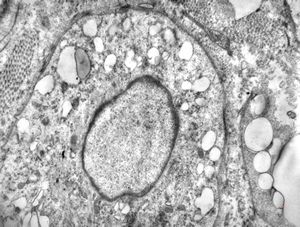

F,32y. | transversally sectioned skeletal muscle cell

mouse skeletal muscle cell - transversal section